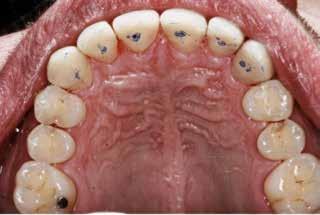

Okklusalt billede af A) over- og B) underkæbe

2. Klinisk ses tydelig slitage ind i dentinen på samtlige tænder fra 6’er til 6’er i begge kæber.

Fig. 2. Clinically, extensive wear into the dentin of all teeth in both jaws is observed.